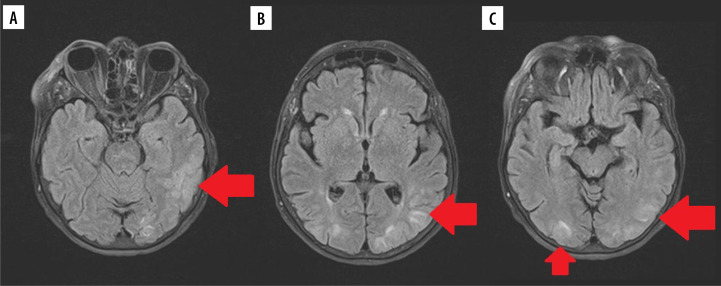

克罗恩病(CD)是临床上越来越常见的疾病。医学的进步延长了患者的生存时间,引入了新的治疗方法,以及疾病本身的性质意味着我们看到越来越多的新的,不寻常的这种疾病的并发症。我们回顾了三例罕见的乳糜泻并发症,重点讨论了影像学检查中可能出现的非典型并发症。乳糜泻及其治疗的并发症可发生在不同的器官和系统,并以非常非特异性的方式表现出来。如果不被注意,它们甚至可能危及生命;因此,在临床实践中,在评估CD患者时考虑其存在的可能性是很重要的。在评估这些人的影像学检查时,我们应考虑不典型体征和影像学特征的可能性,并考虑它们是否与潜在疾病有关。

Crohn's disease (CD) is an increasingly common disease in clinical practice. The progress of medicine, which has resulted in an extension of the survival time of patients, the introduction of new treatment methods, and the nature of the disease itself means that we are seeing more and more new, unusual complications of this disease. We have reviewed three cases of rare complications of CD, with a focus on possible atypical complications that may be seen on imaging studies. Complications of CD and its treatment can occur in various organs and systems, and manifest in very non-specific ways. If unnoticed, they can be even life-threatening; therefore, it is important in clinical practice to take into account the possibility of their presence when evaluating patients with CD. When assessing radiological examinations of these people, we should take into account the possibility of atypical signs and radiographic features, and consider whether they may be related to the underlying disease.